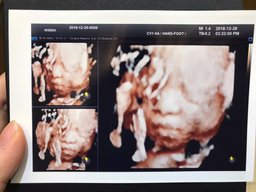

gimemi(25)•in #baby•2560 days ago31주3일 3D초음파 안녕하세요! @gimemi입니다. 오늘도 오랜만에 아가 얼굴을 보고 왔어요~ 28주부터는 2주에 한번씩 검사해야한다고 하더라구요! 이제 수원에서 이것저것 준비를 하고 아예 내려오느라 31주때 방문을 했어요. 저는 그 3주사이에 2키로나 뿔었네요...후 왜이럴까요 ㅠㅠ 흑흑 아가도 1.1...139$0.10gimemi(25)•in baby•2560 days ago31주3일 3D초음파 안녕하세요! @gimemi입니다. 오늘도 오랜만에 아가 얼굴을 보고 왔어요~ 28주부터는 2주에 한번씩 검사해야한다고 하더라구요! 이제 수원에서 이것저것 준비를 하고 아예 내려오느라 31주때 방문을 했어요. 저는 그 3주사이에 2키로나 뿔었네요...후 왜이럴까요 ㅠㅠ 흑흑 아가도 1.1...139$0.10

gimemi(25)•in #baby•2579 days ago28주5일! 탑동이 얼굴확인안녕하세요! @gimemi입니다. 다들 크리스마스 잘 보내셨나요? 벌써 28주 5일이에요.. 남은 날도 70일대로 접어들었죠.. 시간 진짜 빠르네요 ㅠㅠ 드디어 얼굴을 확인할때가 왔어요! 두근두근! 그러나 여전히 까칠한녀석 얼굴을 잘 보여주지 않더라구요 ㅠㅠ 양다리를 폴더로 얼굴까지 접...1410$0.09gimemi(25)•in baby•2579 days ago28주5일! 탑동이 얼굴확인안녕하세요! @gimemi입니다. 다들 크리스마스 잘 보내셨나요? 벌써 28주 5일이에요.. 남은 날도 70일대로 접어들었죠.. 시간 진짜 빠르네요 ㅠㅠ 드디어 얼굴을 확인할때가 왔어요! 두근두근! 그러나 여전히 까칠한녀석 얼굴을 잘 보여주지 않더라구요 ㅠㅠ 양다리를 폴 더로 얼굴까지 접...1410$0.09